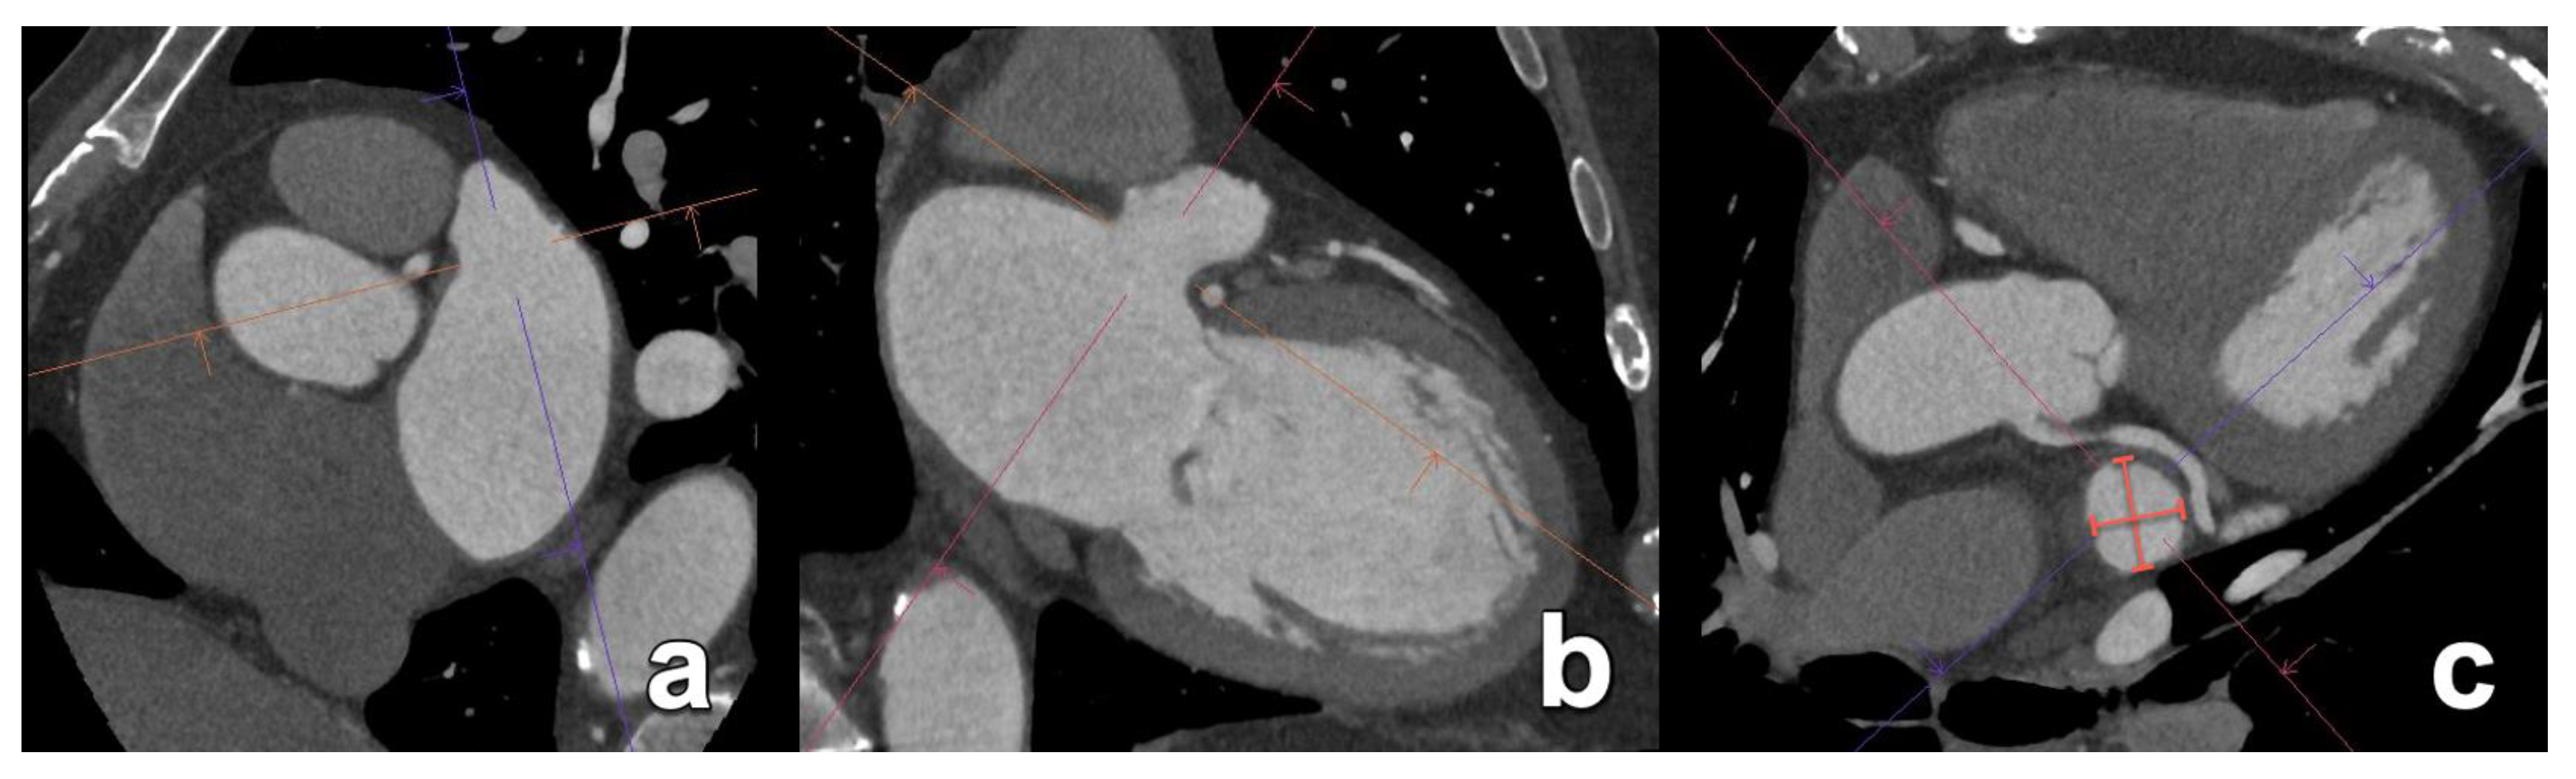

- Naoum, C.; Leipsic, J.; Cheung, A.; Ye, J.; Bilbey, N.; Mak, G.; Berger, A.; Dvir, D.; Arepalli, C.; Grewal, J.; et al. Mitral Annular Dimensions and Geometry in Patients With Functional Mitral Regurgitation and Mitral Valve Prolapse. JACC Cardiovasc. Imaging 2016, 9, 269–280. [Google Scholar] [CrossRef] [PubMed]

- Blanke, P.; Dvir, D.; Cheung, A.; Levine, R.A.; Thompson, C.; Webb, J.G.; Leipsic, J. Mitral Annular Evaluation With CT in the Context of Transcatheter Mitral Valve Replacement. JACC Cardiovasc. Imaging 2015, 8, 612–615. [Google Scholar] [CrossRef] [PubMed]

- Rudzinski, P.N.; Leipsic, J.A.; Schoepf, U.J.; Dudek, D.; Schwarz, F.; Andreas, M.; Zlahoda-Huzior, A.; Thilo, C.; Renker, M.; Burt, J.R.; et al. CT in Transcatheter-delivered Treatment of Valvular Heart Disease. Radiology 2022, 304, 4–17. [Google Scholar] [CrossRef]

- Maggiore, P.; Anastasius, M.; Huang, A.L.; Blanke, P.; Leipsic, J. Transcatheter Mitral Valve Repair and Replacement: Current Evidence for Intervention and the Role of CT in Preprocedural Planning—A Review for Radiologists and Cardiologists Alike. Radiol. Cardiothorac. Imaging 2020, 2, e190106. [Google Scholar] [CrossRef]